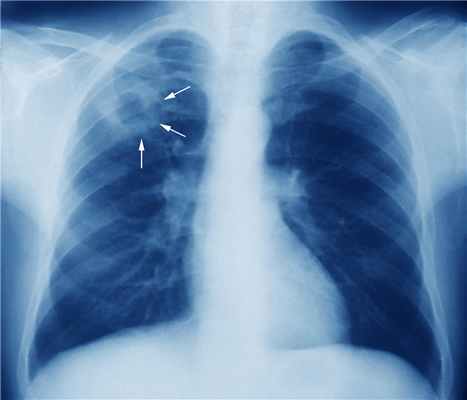

Заражение туберкулезом происходит, как правило, воздушно-капельным путем через частицы (каплеобразные ядра), содержащие M. tuberculosis. Они передаются прежде всего при кашле, пении и других дыхательных движениях людьми, которые больны активным туберкулезом легких или гортани и в чьей слюне содержится значительное количество возбудителя (достаточное, как правило, чтобы получить положительный мазок). Люди с легочными полостными кавернами являются особо заразными из-за большого количества бактерий, содержащихся в каверне.

Контагиозность пациентов с нелечённой активной формой туберкулеза легких широко варьируется. Некоторые штаммы M. tuberculosis являются более заразными, и пациенты с положительными результатами бактериоскопии мазков мокроты являются более заразными, чем имеющие положительные результаты только бактериального посева. Пациенты с кавернами (которые тесно связаны с микобактериальной нагрузкой в мокроте) являются более заразными, чем не имеющие их.